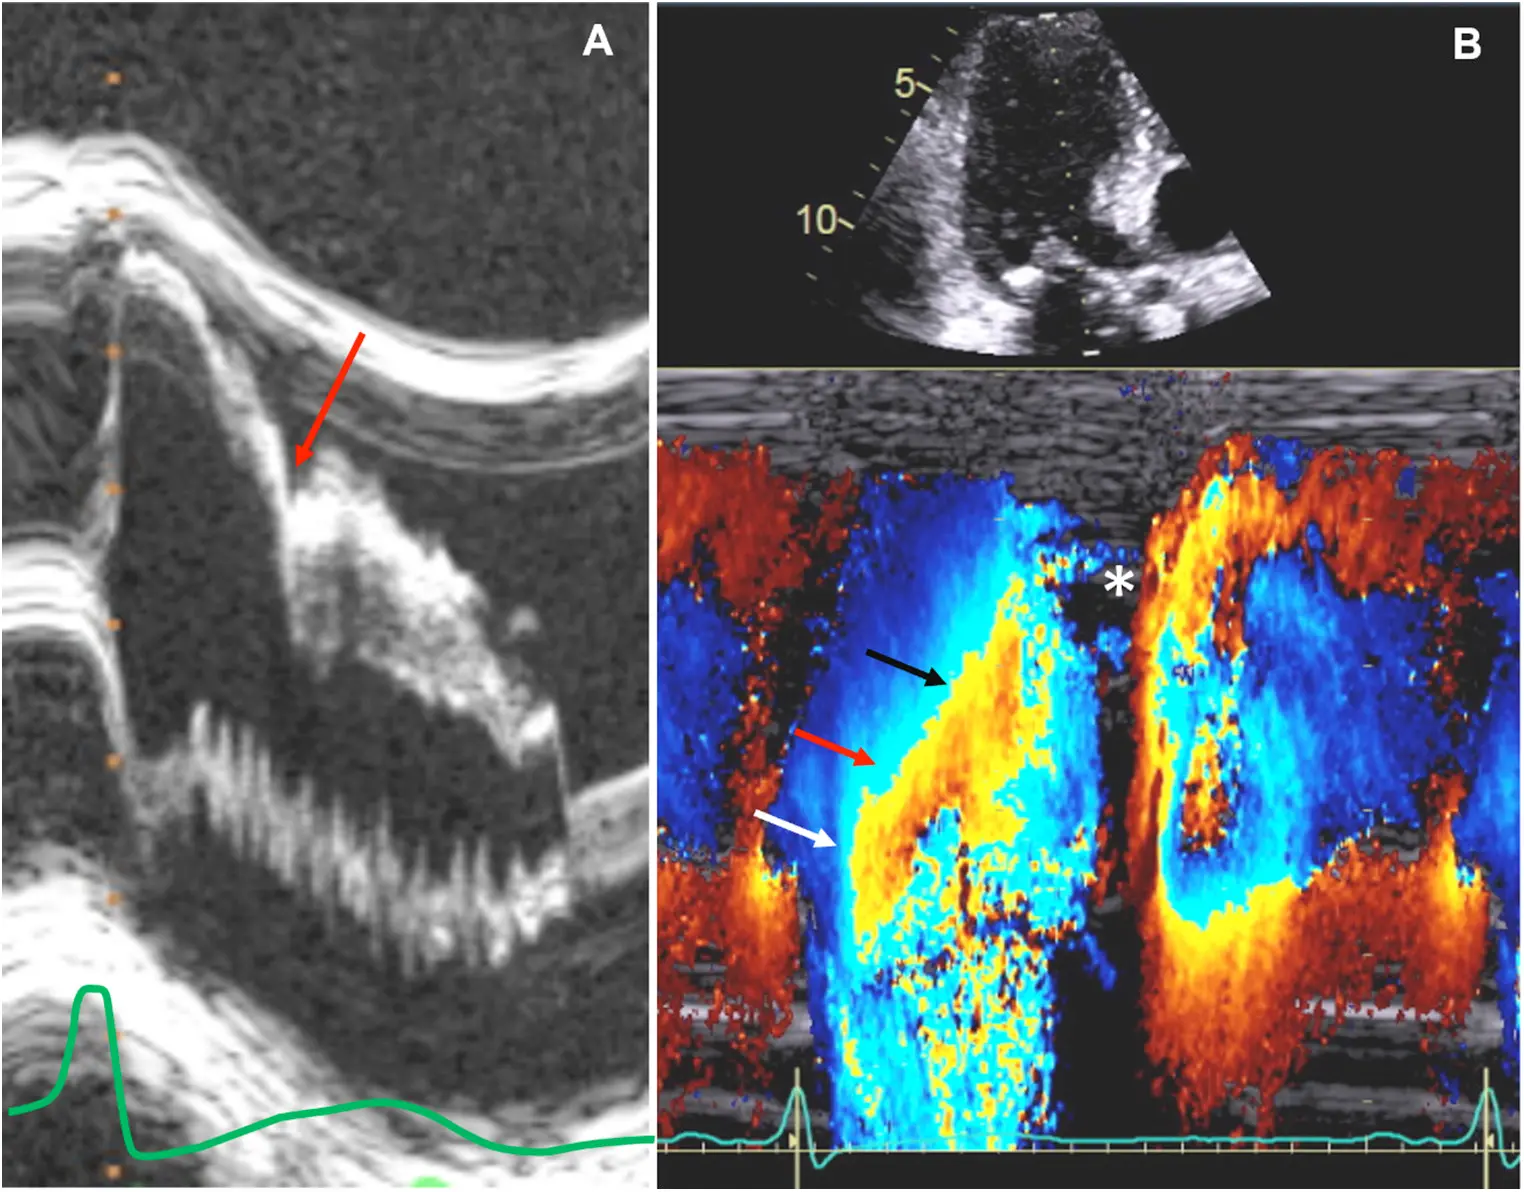

Cardiac MRI in HCM

Offers superior image quality compared to echocardiography and can be crucial in confirming the diagnosis, especially in cases of challenging echocardiographic windows. CMR can also detect myocardial fibrosis, a prognostic indicator in HCM.

In this example, patchy had patchy delayed enhancement suggestive of myocardial fibrosis. Fibrosis is expanding the ECV. Collagen is avidly attracted to gadolinium and holds onto it.

Late Gadolinium Enhancement

- Extensive delayed enhancement is a minor risk factor increasing in importance

- Helpful for resolving difficult AICD decisions when major risk factors are inconclusive

- If LGE ≥ 15%, then may be an AICD candidate